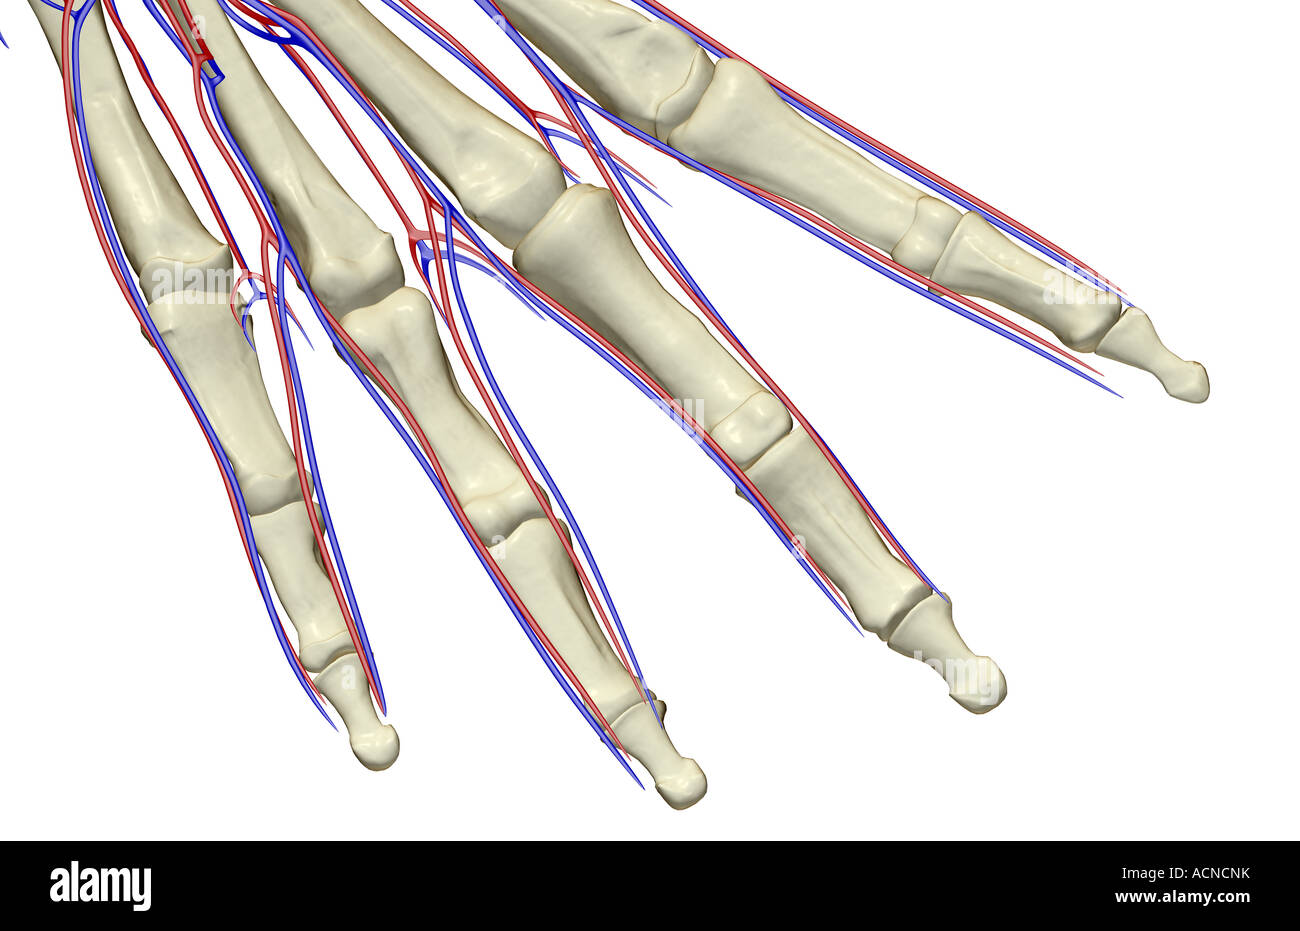

The blood supply of the fingers Stock Photohttps://www.alamy.com/image-license-details/?v=1https://www.alamy.com/stock-photo-the-blood-supply-of-the-fingers-13197438.html

The blood supply of the fingers Stock Photohttps://www.alamy.com/image-license-details/?v=1https://www.alamy.com/stock-photo-the-blood-supply-of-the-fingers-13197438.htmlRFACNCNK–The blood supply of the fingers